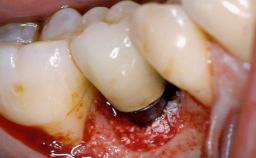

This case describes both a surgical and an anti-infective approach for the management of peri-implantitis, including treatment of the entire dentition to eliminate any deep periodontal pockets that could serve as reservoirs for bacterial re-colonization at the implant site. A 65-year-old female patient was referred to the periodontist in 2013 for assessment and management of an infection at implant 12. On examination, probing depths at implant 12 were 11 mm with suppuration and bleeding on probing.